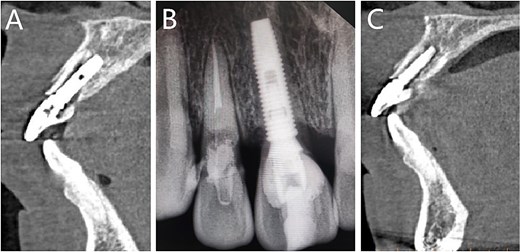

Preoperative dental film revealed 11 and 12 crown-root fracture (Fig. 2A), while results from cone beam computed tomography (CBCT) showed that the lingual fracture line of 11 tooth was located under the alveolar bone, the buccal bone was thin (<1 mm), and the height of alveolar bone was sufficient (Fig. 2B). The lingual side of 12 tooth crown was located at the top of the alveolar crest, with a root length of about 10 mm. No obvious periapical shadow was found (Fig. 2C).

Imaging examinations. (A) The dental film; (B) 11 tooth position in CBCT images; (C) 12 tooth position in CBCT images.